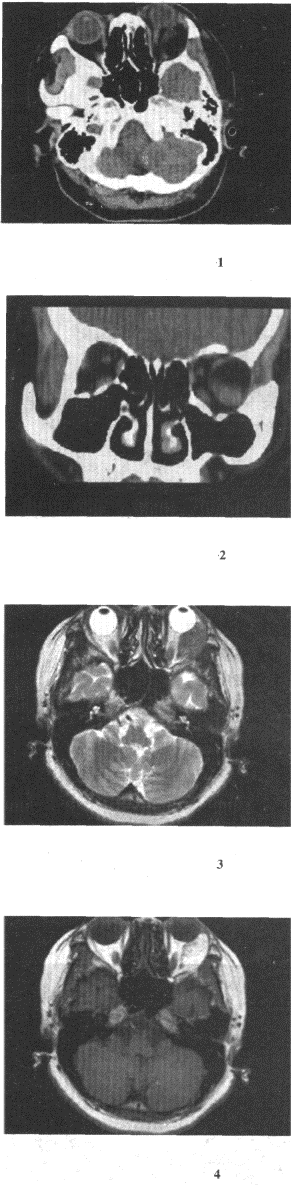

男,17岁,自诉鼻涕中带血3个月,伴耳鸣、听力减退,无发热,影像检查如图,最可能的诊断是() 咽旁脓肿。 鼻咽部恶性淋巴瘤。 鼻咽癌。 小唾液腺混合瘤。 鼻咽部淋巴组织增生。

女,52岁,左眼球突出20余年,Ti、T2均正常,影像检查如图所示,最可能的诊断是()